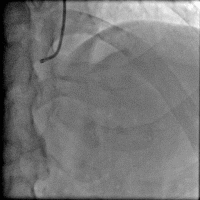

造影结果: 左前降支近段闭塞,回旋支中远段90%狭窄。

手术过程(一): 将Fielder XT 导丝送入回旋支远端真腔,沿回旋支导丝送入Trek 2.5×20 mm球囊到回旋支中段8 atm×10 s预扩,沿导丝Firebird 2.5×29 mm药物支架一枚到回旋支中远段8 atm×12 s释放。

手术过程(三): 微导管支持下ASAHI Gaia 1st 导丝通过前降支真腔。

手术过程(五): 沿导丝送入Firebird 2.5×33 mm药物支架一枚至前降支中段10 atm×12 s释放,沿导丝送入Firebird 3.0×23 mm药物支架一枚至前降支近段14 atm×12s释放。